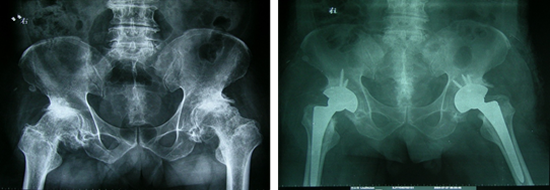

全髖關(guān)節(jié)置換術(shù)